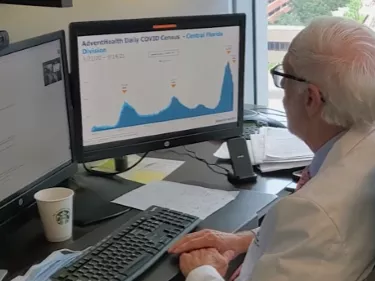

AdventHealth Cancer Institute Advances the Use of CAR T-Cell Therapy for Multiple Myeloma

CAR-T therapies have emerged as new treatment options for certain types of cancer through a one-time infusion that can lead to long-lasting remission.

CAR-T therapies have emerged as new treatment options for certain types of cancer through a one-time infusion that can lead to long-lasting remission.